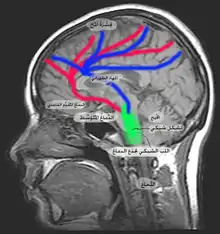

العقل البشري يتكون من ثلاثة أجزاء : المخ، المخيخ وجذع الدماغ.و المخ هو أكبر جزء من الدماغ ويشكل حوالي 85% من إجمالي وزن الدماغ. وهو مقسم إلى نصفين، واحد على كل جانب من الرأس. ضمن المخ تنتج أكثر العمليات العقلية والحسية تعقيدا، مثل الذكاء، والمنطق، والذاكرة، والعواطف، والرؤية، والقدرة على الشعور، الخ. والمخيخ هو جزء صغير ضمن الدماغ ويقع خلف المخ. يلعب دورا أساسيا في التنسيق، والوقوف والتوازن. وجذع الدماغ هو جزء يربط نصفي الكرة الدماغية مع الحبل الشوكي، وهو مسؤول عن السيطرة على العديد من الوظائف البدنية الأساسية، مثل التنفس وضغط الدم والبقاء مستيقظين وفي حالة تأهب.

التنبه أو التيقظ هي وظيفة نظام التنشيط الشبكي الصاعد. التيقظ إلى درجة السهاد (بالإنجليزية: wakefulness) هو شرط أساسي للوعي. يتم تمثيل نظام التيقظ هذا تشريحيا ضمن عدد من الأجهزة في سقيقة جذع الدماغ المنقارية (بالإنجليزية: rostral brainstem tegmentum)، والدماغ البيني (بالإنجليزية: diencephalon) وقشرة المخ (بالإنجليزية: cerebral cortex).[2] من أهم هذه الأجهزة هي العصبونات المنتجة للأسيتيل والكولين, ضمن الأنوية المحيطة بالقصبة (بالإنجليزية: peribrachial nuclei)، والمتكونة من pedunculopontine tegmental والنوى السقيفية الظهرانية الجانبية (بالإنجليزية: lateral dorsal tegmental nuclei). تقوم هذه بإسقاطات منقارية ضمن ممرين رئيسيين:

- مسلك ظهري يتشابك مع النوى المهادية غير المحددة ضمن الخط الناصف، والتي بدورها ترسل أسقاطا غلوتامينيلي (بالإنجليزية: glutaminergic) لمناطق واسعة من قشرة المخ

- مسلك بطني الطريق من سقيقة جذع الدماغ المنقارية التي تصل إلى الدماغ المُقَدَّم القاعدي (بالإنجليزية: basal forebrain)، وخاصة الوطاء الخلفي (بالإنجليزية: posterior hypothalamus)، حيث تقوم محطات محورية بالتأثير على العصبوات التي تنتج مركبات أمينية مثل الهيستامين وغيرها لتنتج في النهاية هرمون الأوركسين (بالإنجليزية: orexin). هذه بدورها تساهم في التيقظ القشري.

و عليه فنظام التنشيط الشبكي الصاعد هو نظام معقد ذو مسارات مكررة تشارك في التيقظ وإدامة السهاد. يمكن مما سبق فهم سبب الانتعاش في نظام التنشيط بعد الغيبوبة الأولية بعد 3 أسابيع (تقريبا) من بداية غيبوبة في معظم المرضى.